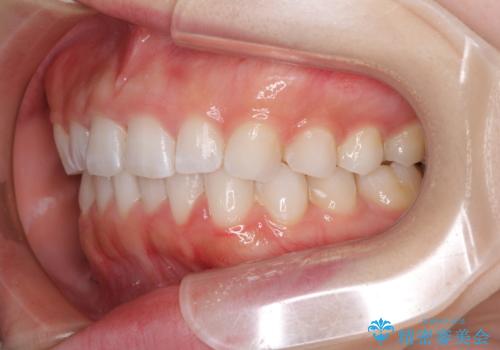

デコボコと深い咬み合わせの改善 インビザラインによる矯正治療

- 口元のデコボコと深い咬み合わせ(ディープバイト)を気にして来院された患者様です。

インビザラインによる上下歯列の拡大と、IPR(歯と歯の間を削る)にるスペースの獲得により、口元のデコボコとディープバイトを改善することとしました。

インビザラインは、装着していない時間がどれだけ短いかが、治療期間を大きく左右します。こちらの患者様は1日22時間以上、毎日欠かさず装着してくださったため、1年強という短期間で満足のいく歯列に整えることができました。